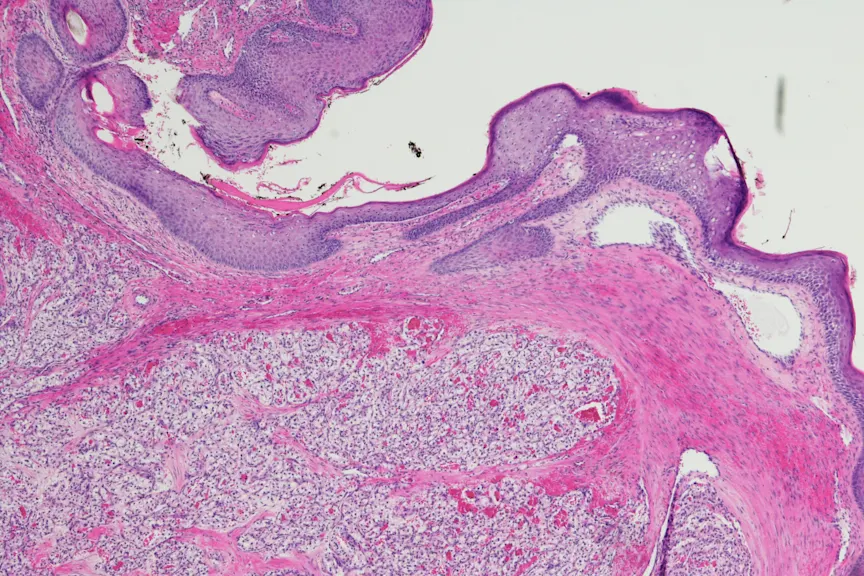

Hand-Foot综合症

众所周知,化疗会引起副作用,手足综合征就是其中之一。“你手脚上的皮肤细胞对这种靶向治疗非常敏感,”曹博士说。“一些患者可能会开始经历手掌、脚掌、手指和脚趾的皮肤变化和疼痛。当它变得更严重时,会损害正常的手部功能和行走。”他要求患者在开始针对性治疗时,每天两次在手脚上涂抹优色林修护霜,这可能会使他们更容易患上手足综合征。